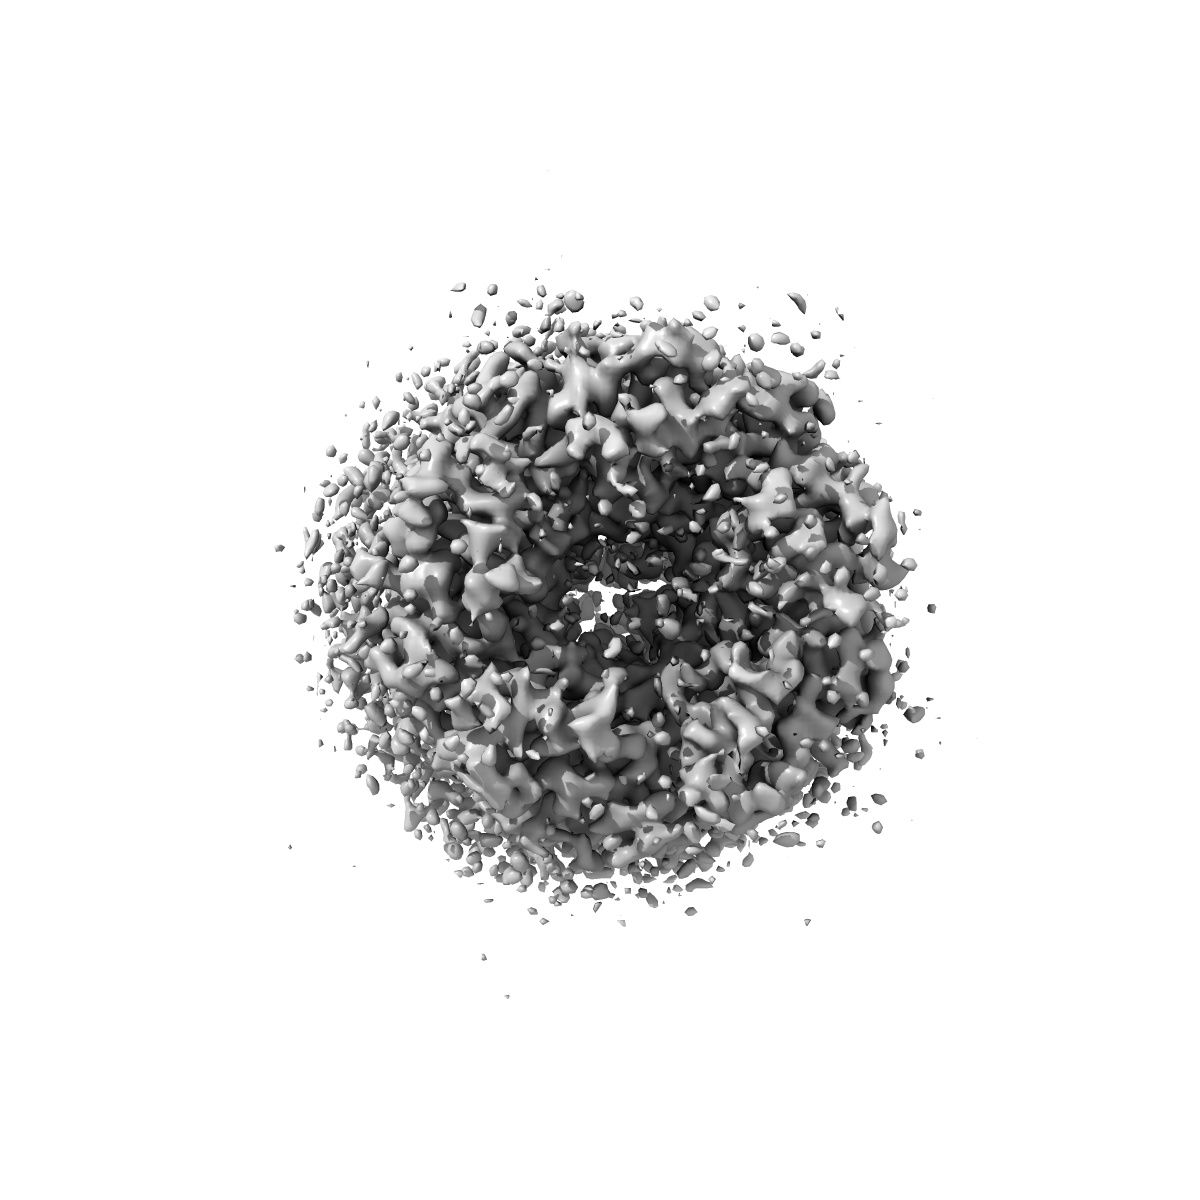

Cyro-EM structure of human Glycine Receptor alpha2-beta heteromer, strychnine bound state, 3.8 Angstrom

Sample Organism: Homo sapiens

Sample: Glycine receptor alpha2-beta heteromer with strychnine, 3.8 Angstrom

Fitted models: 7l31

Characterization of the subunit composition and structure of adult human glycine receptors

Yu H, Bai X-C, Wang W

(2021) Neuron , 109 , 2707 - 2716